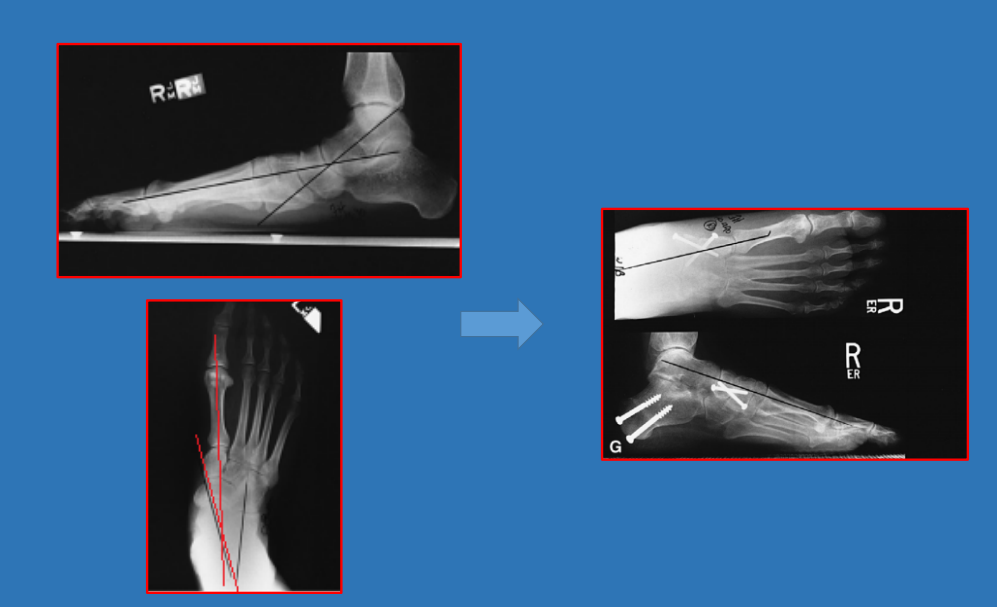

21 前足—拇外翻

拇外翻角Hallux valgus angle,HVA(metatarsophalangeal angle,MTP-1)

正常 < 15°

轻度 < 20°

中度 20°~40°

重度 > 40°

第一、二跖骨间角Intermetatarsalangle,IM 1-2

正常 < 9°

轻度 9°~11°

中度 11°~16°

重度 > 16°

跖骨远端关节角(DMAA)正常<8°